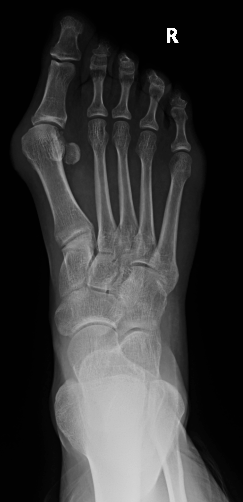

Pijn bij kinderen aan de binnenzijde van de voetboog, kan soms te wijten zijn aan een extra botkern die zich daar gevormd heeft tijdens de groei. Dit is een goedaardig en aangeboren fenomeen. De pees die de voetboog opgetrokken houdt (tibialis posterior pees) hecht nu niet alleen aan op het scheepsvormige beentje (os naviculare), maar ook deels op het extra botje (os tibiale externum). Dit geeft dan pijnklachten en de voet ziet eruit als een platvoet. Vaak drukt dit extra botje tegen de leest van de schoen, en is dan nog pijnlijker. Soms ontstaan de klachten pas na een onschuldig ongeval (bv. enkel of voet omgeslagen). Een andere naam voor deze aandoening is “pre-hallux syndroom”.

Aangeboren. Ontdekken we pas als het pijn doet en we RX genomen hebben.